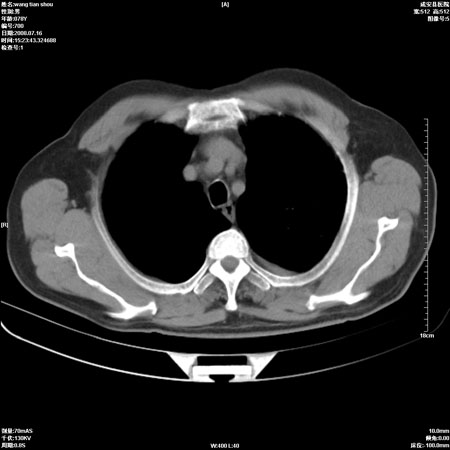

以下是引用qingjing在2008-7-16 19:55:00的发言:[br]1、左上肺不张并堵塞性炎症,建议支气管镜详查;[br]2、左侧胸腔少量积液。

以下是引用wzr在2008-7-16 20:26:00的发言:[br]左肺肺不张伴阻塞性肺炎!另:左侧胸腔少量积液。建议纤支镜检查!